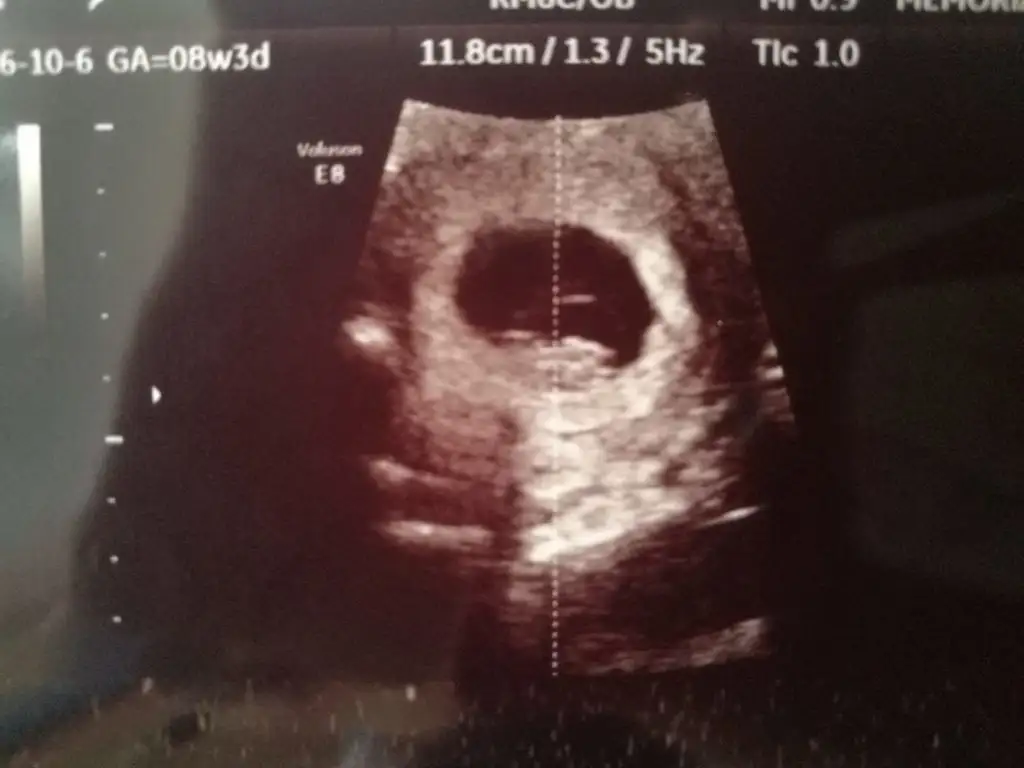

Kız benceEki Görüntüle 2277369 Acaba benim bebişimin Cinsiyeti ne olabilir 8 haftalık Karından

Evet canım sağda duruyor teoriye göre öyleBu teoriye göre bizim kızmı oluyo şimdi arkadaslarkarında usg ile bakıldı

Bu dogrumu canm benim 7 haftalik teoriye solda karinda erkek zaten gissedyrdm dr birgun onceerkek ikili testte kiz dedi anlamadk 14 haftalgm ins degsr9+4 göre erken sekil almış erkek diyorum